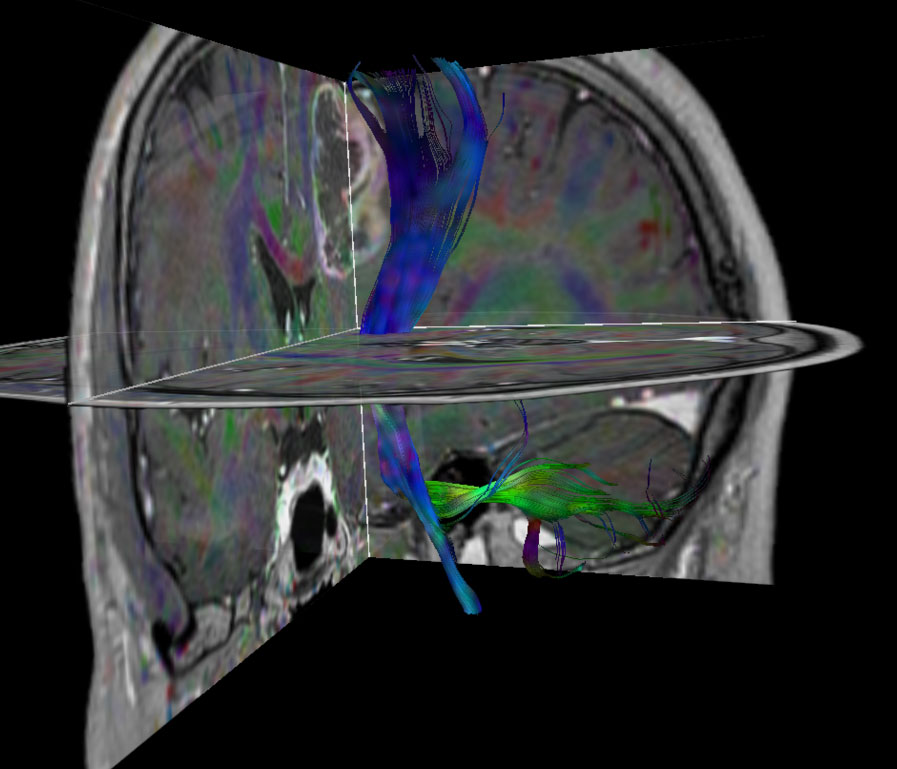

Patient with a revasculerized area with small bleedings. Diagnosed as malignant glioblastoom.

DTI FiberTrak